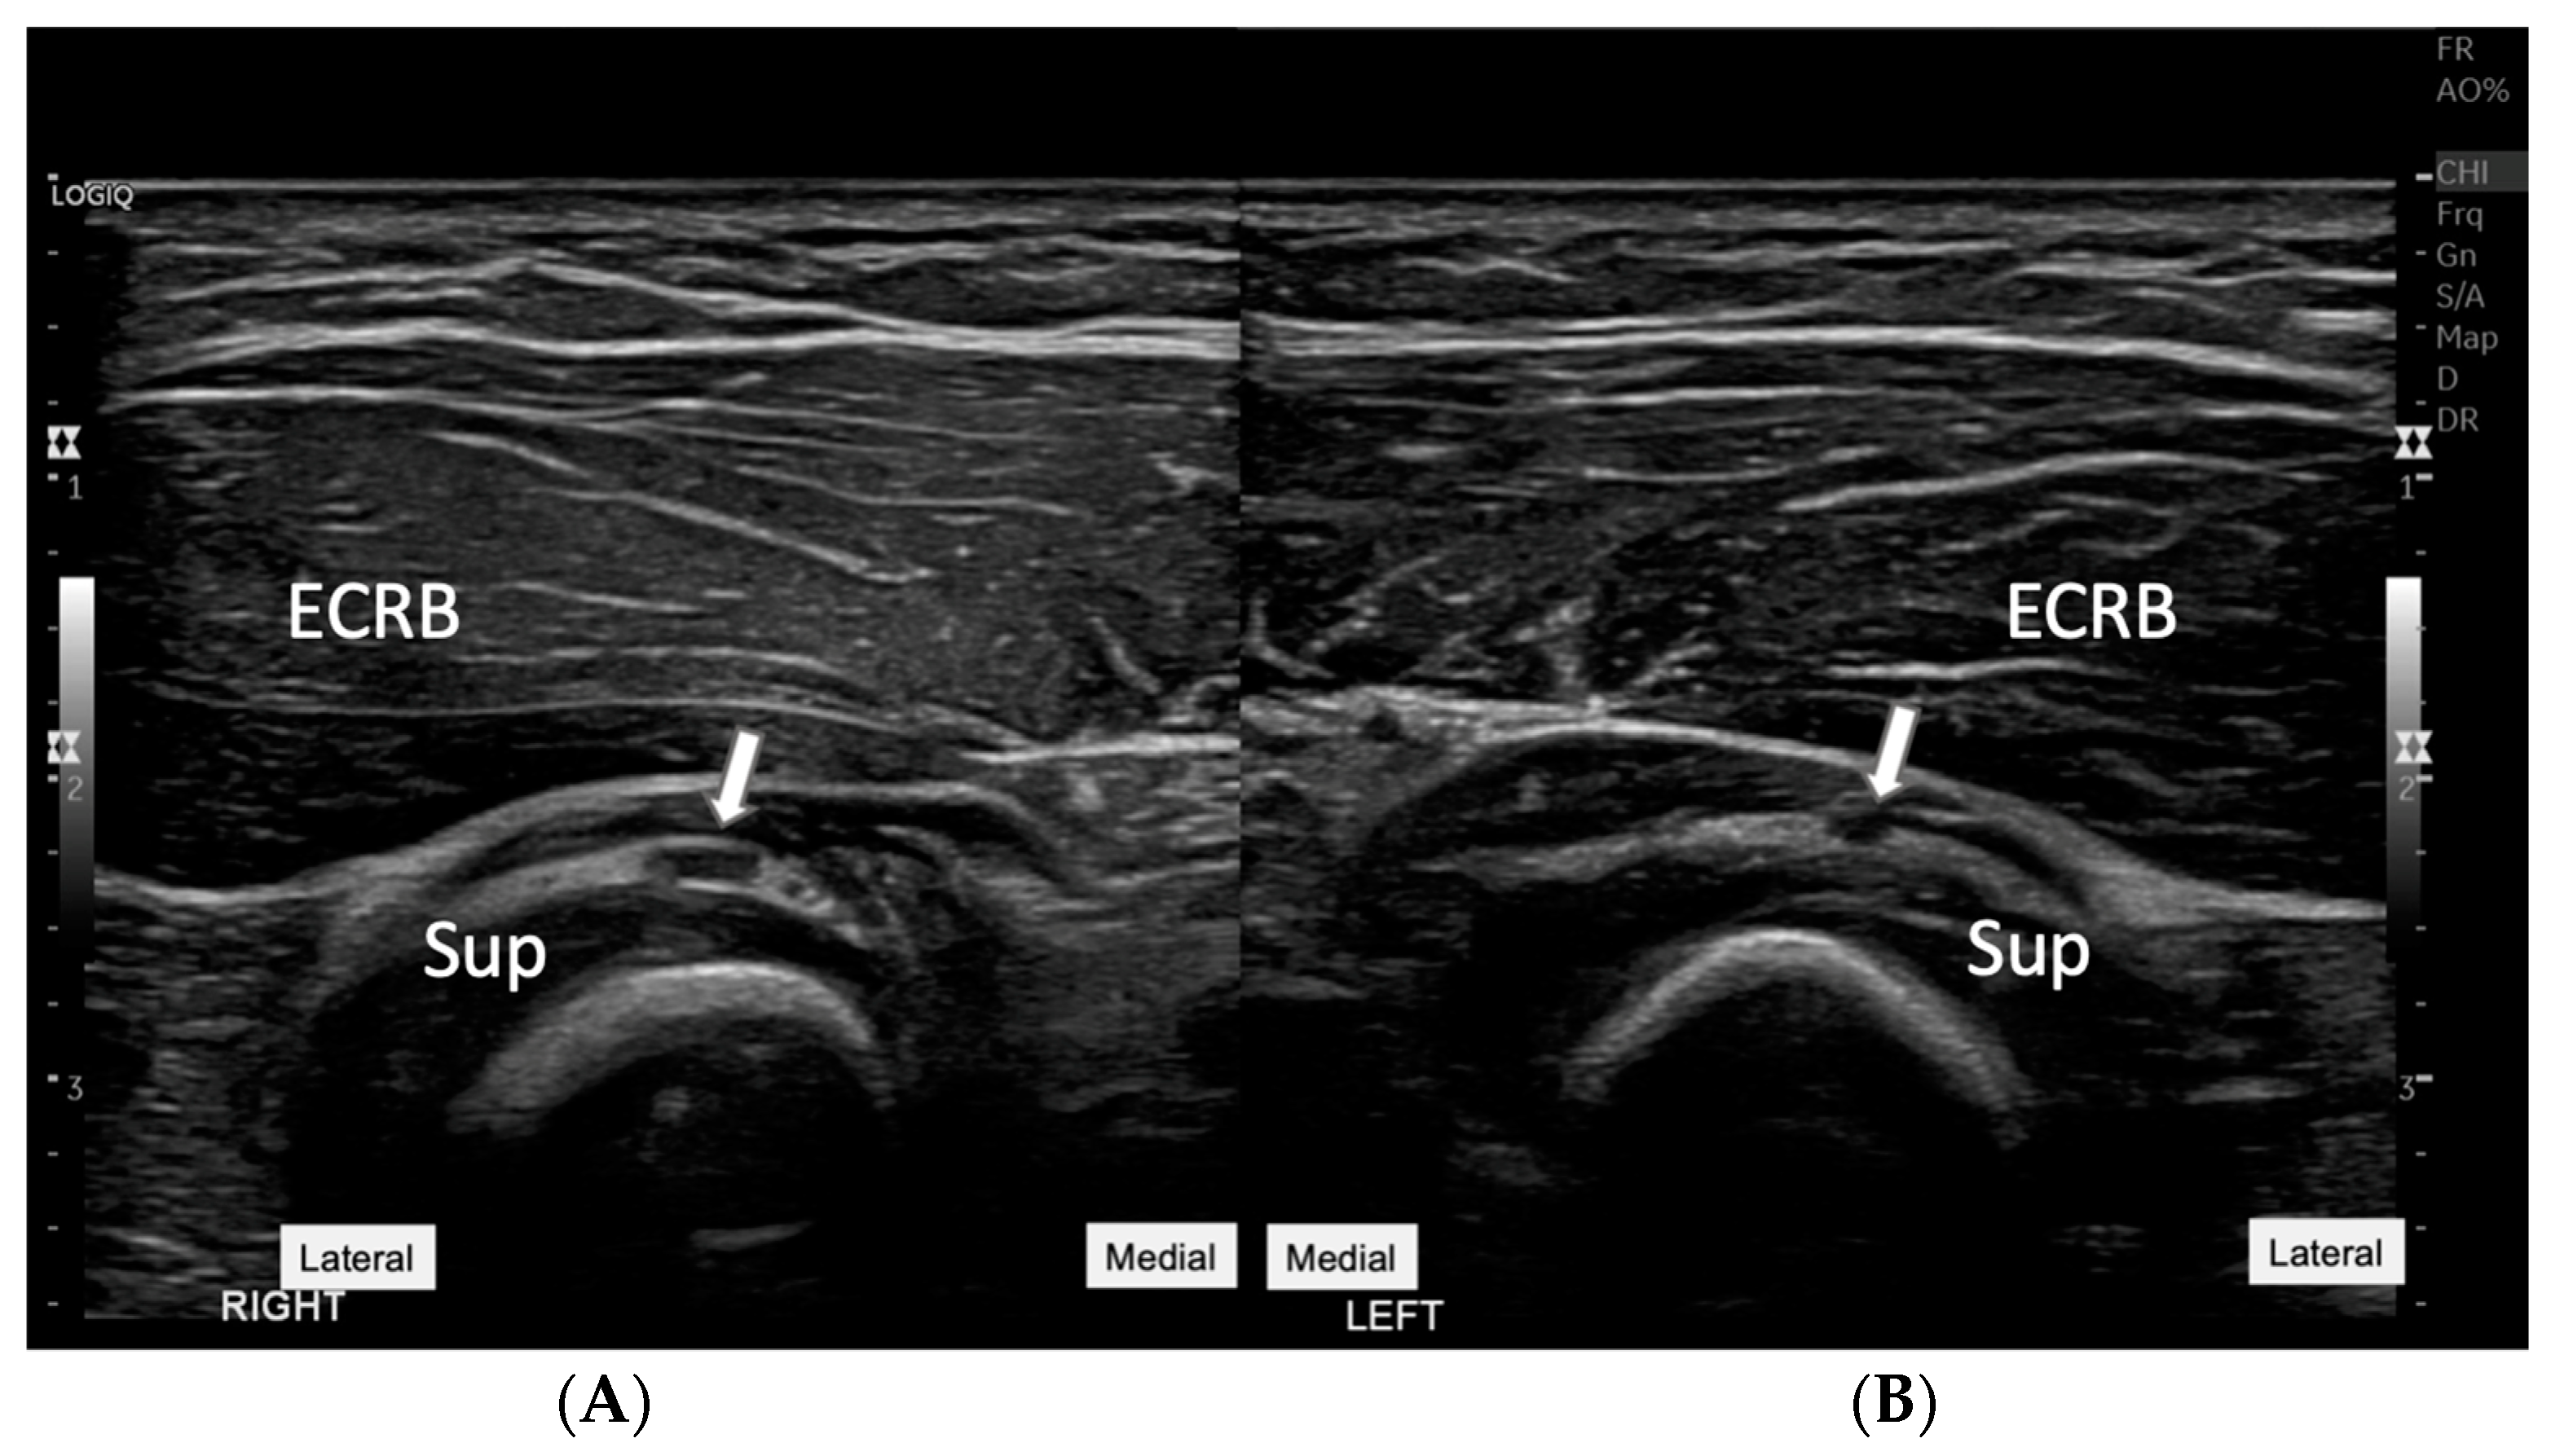

Figure 3.

Comparative ultrasound images of the affected right forearm (

A)

with the unaffected left side (

B). This figure presents side-by-side images of both the right and left forearms, specifically focusing on the region of the supinator muscles. The arrows on each image point to the PIN as it courses through the supinator muscle (Sup). On the right side (

A), there is a noticeable swelling of the PIN at the site of the lesion. In contrast, the left side (

B) shows a normal appearance of the PIN without swelling, serving as a control reference. This comparative view underlines the diagnostic value of ultrasound in assessing asymmetrical nerve conditions and supports clinical findings of neuropathy on the affected side. ECRB: Extensor carpi radialis brevis. An ultrasound-guided aspiration was performed, carefully avoiding the PIN (